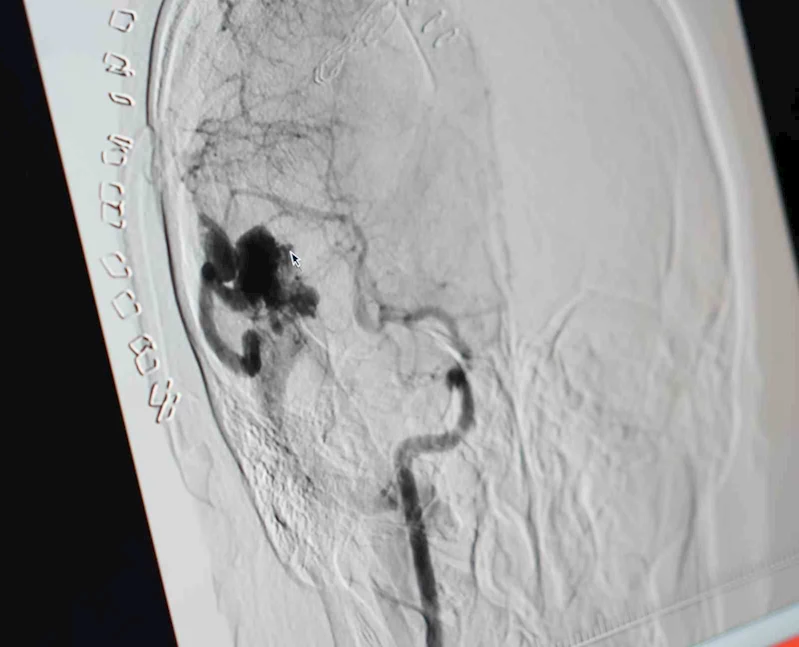

Samsun'da beynindeki 4 santimetre çapındaki damar yumağı (intrakranial arteriovenöz malformasyon) nedeniyle koma halinde Samsun Eğitim ve Araştırma Hastanesine kaldırılan genç kız, ameliyat edildikten sonra hastaneden yürüyerek çıktı.

Samsun'da yaşayan 23 yaşındaki Bahar Köse, şiddetli baş ağrısı ve şuur bulanıklığı şikayetiyle Çarşamba Devlet Hastanesi'ne başvurdu. Hastaya çekilen bilgisayarlı tomografide beyin sağ yarımında kranial kanama ile uyumlu durumlar tespit edilmesi üzerine hasta, Sağlık Bakanlığı, Samsun İl Sağlık Müdürlüğü'ne bağlı Eğitim ve Araştırma Hastanesi'ne sevk edildi. Burada Beyin ve Sinir Cerrahisi Uzmanı Doç. Dr. Vaner Köksal tarafından kanamaya yönelik operasyon gerçekleştirildi. Operasyon esnasında hastada kafa içi damar yumağı tespit edildi. Hastanın mevcut kanaması boşaltılarak girişimsel radyoloji tarafından anjiyografi işlemi yapıldı. Hastanın anjiyografi işleminde beyin sağ yarımındaki kafa içi damar yumağı detaylıca ortaya konuldu. Beyin cerrahisi ve girişimsel radyoloji tarafından birlikte yapılan değerlendirmeler sonucunda arteriovenöz malformasyonun endovasküler (damar içerisinden) yöntemle tedavisinin yapılmasına karar verildi. Girişimsel Radyoloji Uzmanı Doç. Dr. Hasan Gündoğdu ve ekibi tarafından hastanın ameliyatı başarıyla gerçekleştirildi.

Yapılan işlem hakkında bilgi veren Girişimsel Radyoloji Uzmanı Doç. Dr. Hasan Gündoğdu, "Hastamız Çarşamba Devlet Hastanesi'ne beyine kanaması nedeniyle başvurdu. Burada yapılan tomografisinde beyin için bir kanama tespit edildi. Hastamız akabinde hastanemize gönderildi. Burada Dr. Vaner Köksal hocamız hastamızı opera etti ve kanamasını boşalttıktan sonra orada damar yumağı tespit edildi. Sonrasında hastamızı girişimsel radyolojik ünitemize alarak anjiyosunu ardından da işlemini gerçekleştirdik. 2 ay aradan sonra hastanın genel durumu iyidir. Şu anda normal konuşmasını, fonksiyonlarını gerçekleştirebiliyor. Bu operasyonu hem beyin cerrahisi ile yapabilme adına hem de hastanemizde ilk defa böyle bir beyin yumağı tedavisini sağlamak bize gurur verdi. Bundan sonrada hastalarımızı bu şekilde tedavi etmeye gayret göstereceğiz. Bu hastalar intrakranial kanama geçirmesi nedeniyle gerek felç kalma, gerekse ölüm riski yüksek hastalardır. Hasta bir kez daha kanasaydı muhtemelen ölümle sonuçlanabilecek bir durumla karşı karşıya kalabilirdi" dedi.

Beyin ve Sinir Cerrahisi Uzmanı Doç. Dr. Vaner Köksal ise "Kanı boşaltıp, beyni rahatlatıcı bir ameliyat gerçekleştirdim. Buna sebep olan problemi kendi gözlerimle gördüm. O an ameliyatla zorlayarak çıkartabilirdik ama beyin dokusuna daha çok zarar verebilirdik. Damar yumağı küçültebilecek bir işleme karar verdik. Dr. Hasan beyden yardım istedim. Ameliyat sonrası beyinde oluşan bir damar yumağı için, bu damar yumağını besleyen damarları Hasan Bey kapattı. Kanamanın tekrarını engellemiş olduk. Hastamıza bu işlem sırasında tek bir yansıması oluşmadı. Başarılı şekilde bir damar yumağını bertaraf etmiş olduk" diye konuştu.